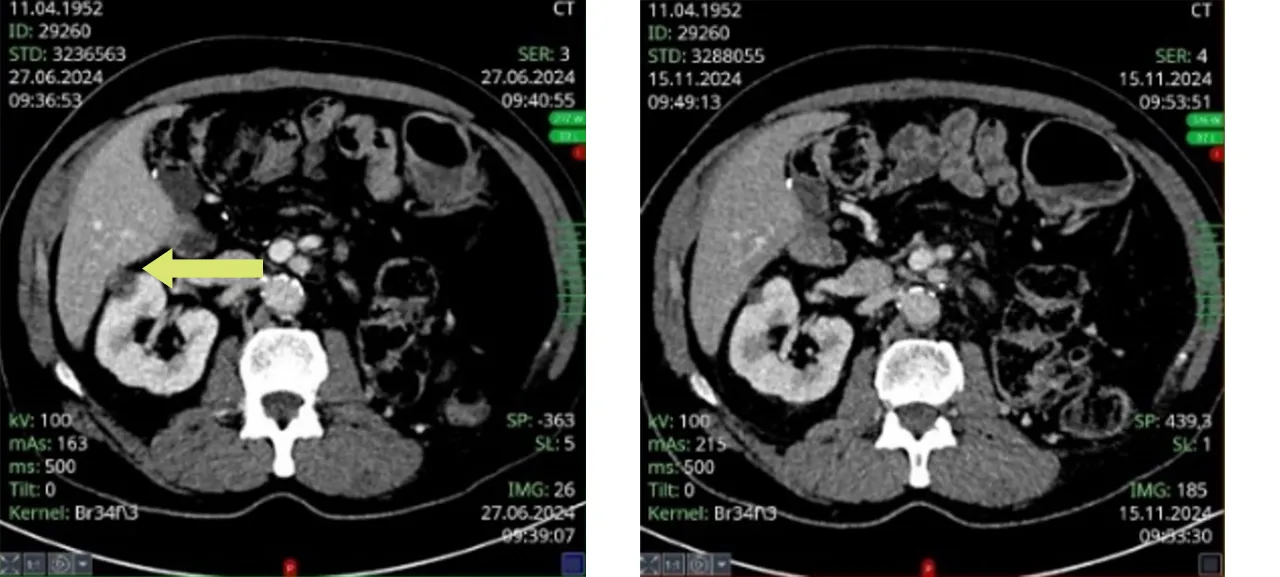

Слева: В этом случае 72-летнему пациенту с раком правой почки было проведено радиохирургическое лечение в июне 2024 года.

Справа: через 5 месяцев после терапии CyberKnife за один сеанс (продолжительность лечения: 30 минут) на МРТ-снимке видно значительное уменьшение объема опухоли примерно на 80% и ее полное излечение. Регулярные проверки теперь можно один раз в год.

Справа: через 5 месяцев после однократной сессии терапии CyberKnife (продолжительность лечения: 30 минут) МРТ показала значительное уменьшение объема опухоли примерно на 80 %, и она уже не обнаруживается. Теперь можно проводить регулярные контрольные обследования раз в год.